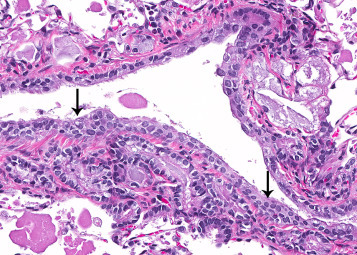

Mesotheliomas in the thoracic cavity arise from the mesothelial cells lining the pleura. Primary spontaneous pleural mesotheliomas are rare in rats. They have been induced by exposure to various fibers and chemicals (Greaves et al., 2013, Kane, 2006, Doi et al., 2010, Wagner, 1962, Stanton and Wrench, 1972). Grossly, pleural mesotheliomas may be focal or diffuse along the pleura, and grow by expansion rather than infiltration. In rats, all mesotheliomas are considered malignant. Histologically, pleural mesotheliomas may be classified as epithelial, mesenchymal, or a mixture of both (Stanton and Wrench, 1972, Wagner and Berry, 1969, Davis, 1979). Epithelial mesotheliomas are the most common histologic type and may be classified as papillary, tubular, tubulopapillary, or solid. The papillary type is most prevalent and are usually exophytic consisting of single or multiple, irregularly branching, frond-like proliferations of well-vascularized collagenous to fibrous connective tissue stroma lined by a single to several layers of uniformly small, low cuboidal to polyhedral mesothelial cells (Figure 23.48, Figure 23.49 ). The tubular type consists of large atypical pleomorphic cells that form glandular-like structures. The solid type can be quite extensive, florid proliferations composed of abundant prominent stroma with extensive areas of pleomorphic mesothelial cells occurring as clusters, tubular structures, and solid sheets on the surface and within the masses. The mesenchymal variant resembles fibrosarcomas and consists of interlacing bundles of spindle shaped cells that resemble fibroblasts. The mixed variant has both epithelial and mesenchymal components occurring together in varying proportions.

Figure 23.48.

Malignant mesothelioma of the lung characterized by multifocal papillary neoplastic mesothelial cells on the surface of the pleura.

Figure 23.49.

Higher magnification of Fig. 23.48. Note characteristic multiple, frond-like proliferations lined by a single layer of uniformly small, low cuboidal to polyhedral mesothelial cells associated with fibrous thickening of the pleura.